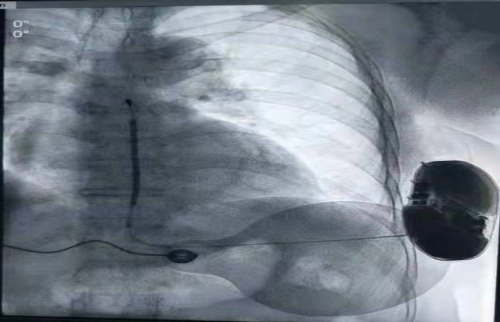

9月17日,中南大学湘雅三医院心血管内科心律失常与心力衰竭亚专科张志辉教授及叶飞博士团队成功为一名猝死高危的Long QT综合征患者植入全皮下植入式心律转复除颤器(S-ICD)。本次植入病例为湖南省首例,开创了湖南省猝死预防新纪元。